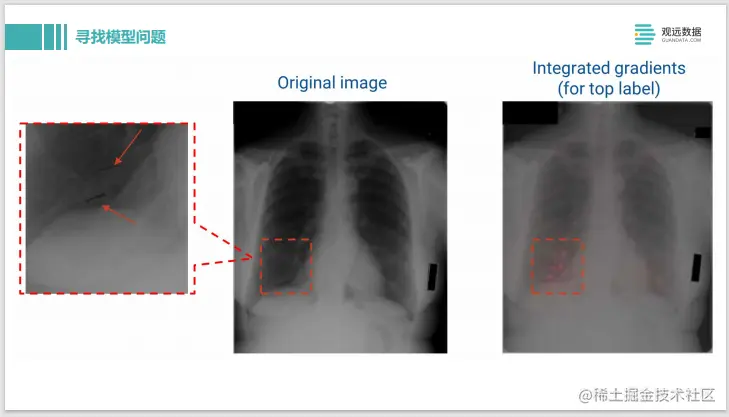

这是利用IG – Integrated Gradients,做 X光片的疾病诊断。可以看到原始输入的图片是左边。输出的 label是这个人有疾病,我们用了 IG去做解释后,可以看到右边这边有一些粉红色的高亮,这表示在这些像素点上的模型认为样本被分类为有问题,是贡献度最大的像素点。

图片

我们可以再把像素点放大,看看模型到底是做了什么样的判断。结果发现这个其实是上面有两条用黑色记号笔画的线,应该是医生在诊断过程中看了X光片,确诊出来有问题,就在这边画了两条马克笔的线,那模型学到的是医生的标记,并不是学到了病理组织的 pattern,所以模型的判断其实是有问题的。这样就可以很方便的通过模型解释的方法去找到模型中的一些弱点。